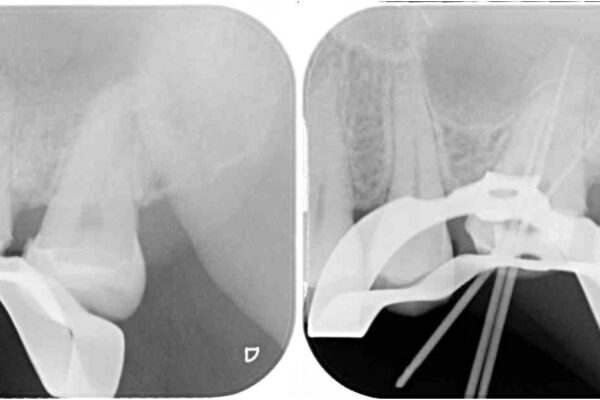

レントゲン写真から、神経組織近くにまで大きな修復物が認められました。

叩いたり、冷熱や電気刺激によるテストを行ったりとしましたが、炎症の状態は芳しくなく、根管治療を行う前提で処置を行うこととしました。

治療途中

• 奥歯がズキズキと痛む 奥歯の虫歯治療 治療途中画像